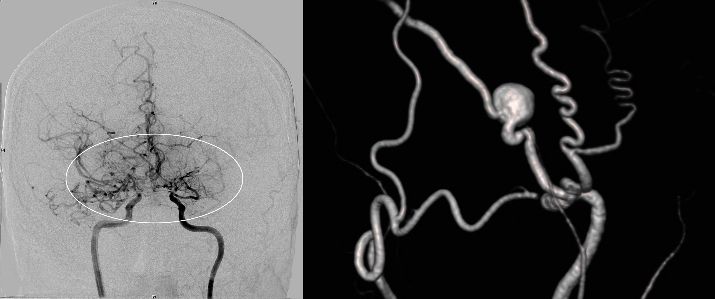

Die konventionelle cerebrale Angiographie ist die wichtigste Untersuchung zur Diagnosestellung der Moyamoya Krankheit. Diese Untersuchung ist zu vergleichen mit einer Herzkatheteruntersuchung, eben nur mit Darstellung der Hirnarterien. Bei Moyamoya-Patientinnen und Patienten werden, im Gegensatz zu Routineuntersuchungen bei anderen cerebralen Erkrankungen, selektiv die vordere und hintere Zirkulation des Gehirns dargestellt, sowie auch die Versorgung der extrakranialen Gefäße. Diese umfassende Darstellung ist besonders wichtig, um die vollständige Ausdehnung der Erkrankung zu erfassen und alle möglicherweise veränderten Blutflüsse im Gehirn zu verstehen. Je nach Befund werden die Engstellen der Hirnarterien, sowie auch mögliche begleitende Veränderungen selektiv hochauflösend dreidimensional dargestellt. Es ist wichtig zu erwähnen, dass die Moyamoya Krankheit nicht über eine Katheterintervention (Ballonaufweitung der Engstelle) behandelt werden kann und darf. Dies haben mehrere Studien gezeigt.

Angiographie beidseitige Moyamoya Krankheit

Konventionelle Angiographie eines Patienten mit beidseitiger Moyamoya Krankheit (links). 3-dimensionale Darstellung eines Aneurysmas einer jahrelang stark beanspruchten Spontan-Kollaterale (rechts).

Angiographie zur Darstellung der zusätzlichen Blutversorgung des Gehirns

1 Jahr postoperativ: Angiographie zur Darstellung der zusätzlichen Blutversorgung des Gehirns über den Bypass (linke Seite) in Ergänzung zu der unzureichenden Versorgung über die innere Halsschlagader (rechte Seite).